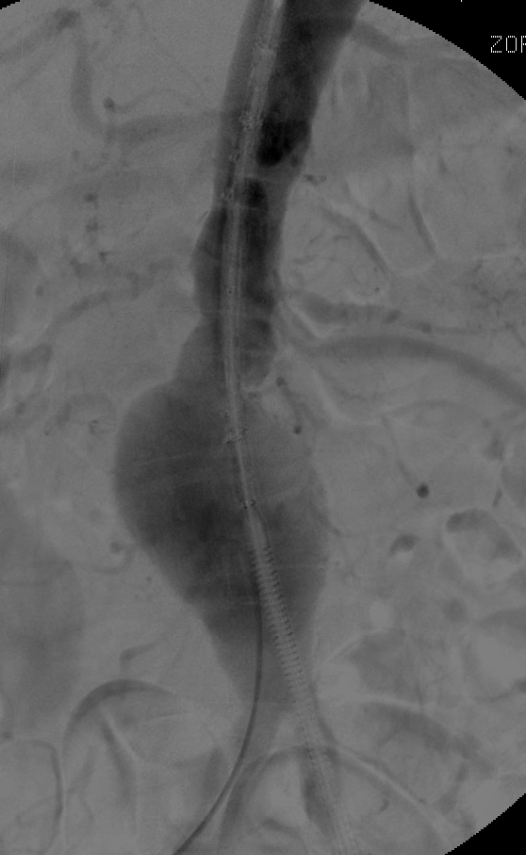

Anhand dieser hochauflösenden 3D-Rekonstruktionen aus dem CT können Sie den Erfolg der Behandlung Schritt für Schritt nachvollziehen. Wir nutzen minimal-invasive, endovaskuläre Verfahren, um die gefährliche Erweiterung der Hauptschlagader dauerhaft auszuschalten – häufig ohne den Brustkorb oder Bauchraum großflächig eröffnen zu müssen.

Links sehen Sie das gefährliche Aneurysma als 3D-Modell. Rechts der Blick des Operateurs: Das Kontrastmittel markiert genau den Verlauf der Aorta und zeigt, wie kritisch die Erweiterung ist.

Links wird der Stent-Graft präzise positioniert und entfaltet. Rechts sehen Sie das Ziel der Behandlung: Das Blut fließt sicher durch die Prothese, das Aneurysma ist vom Blutstrom entkoppelt und damit weitgehend entschärft.